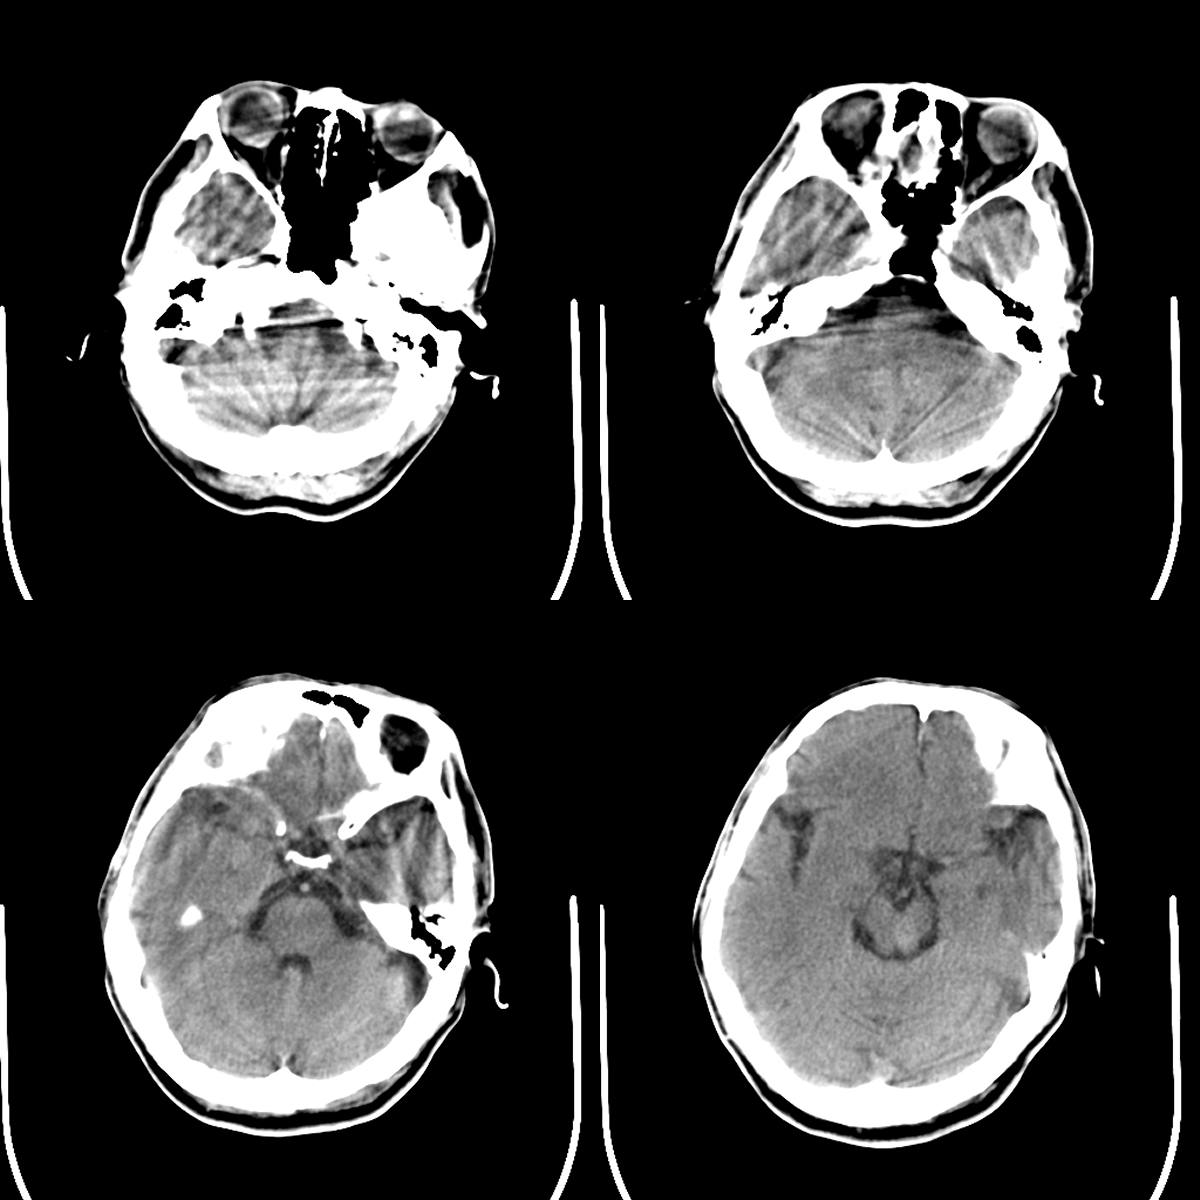

以下是引用358450m在2008-8-3 14:01:00的发言:[br]脑干血管畸形

以下是引用子十在2008-8-3 15:23:00的发言:[br]支持脑干血管畸形,请再薄层扫描。